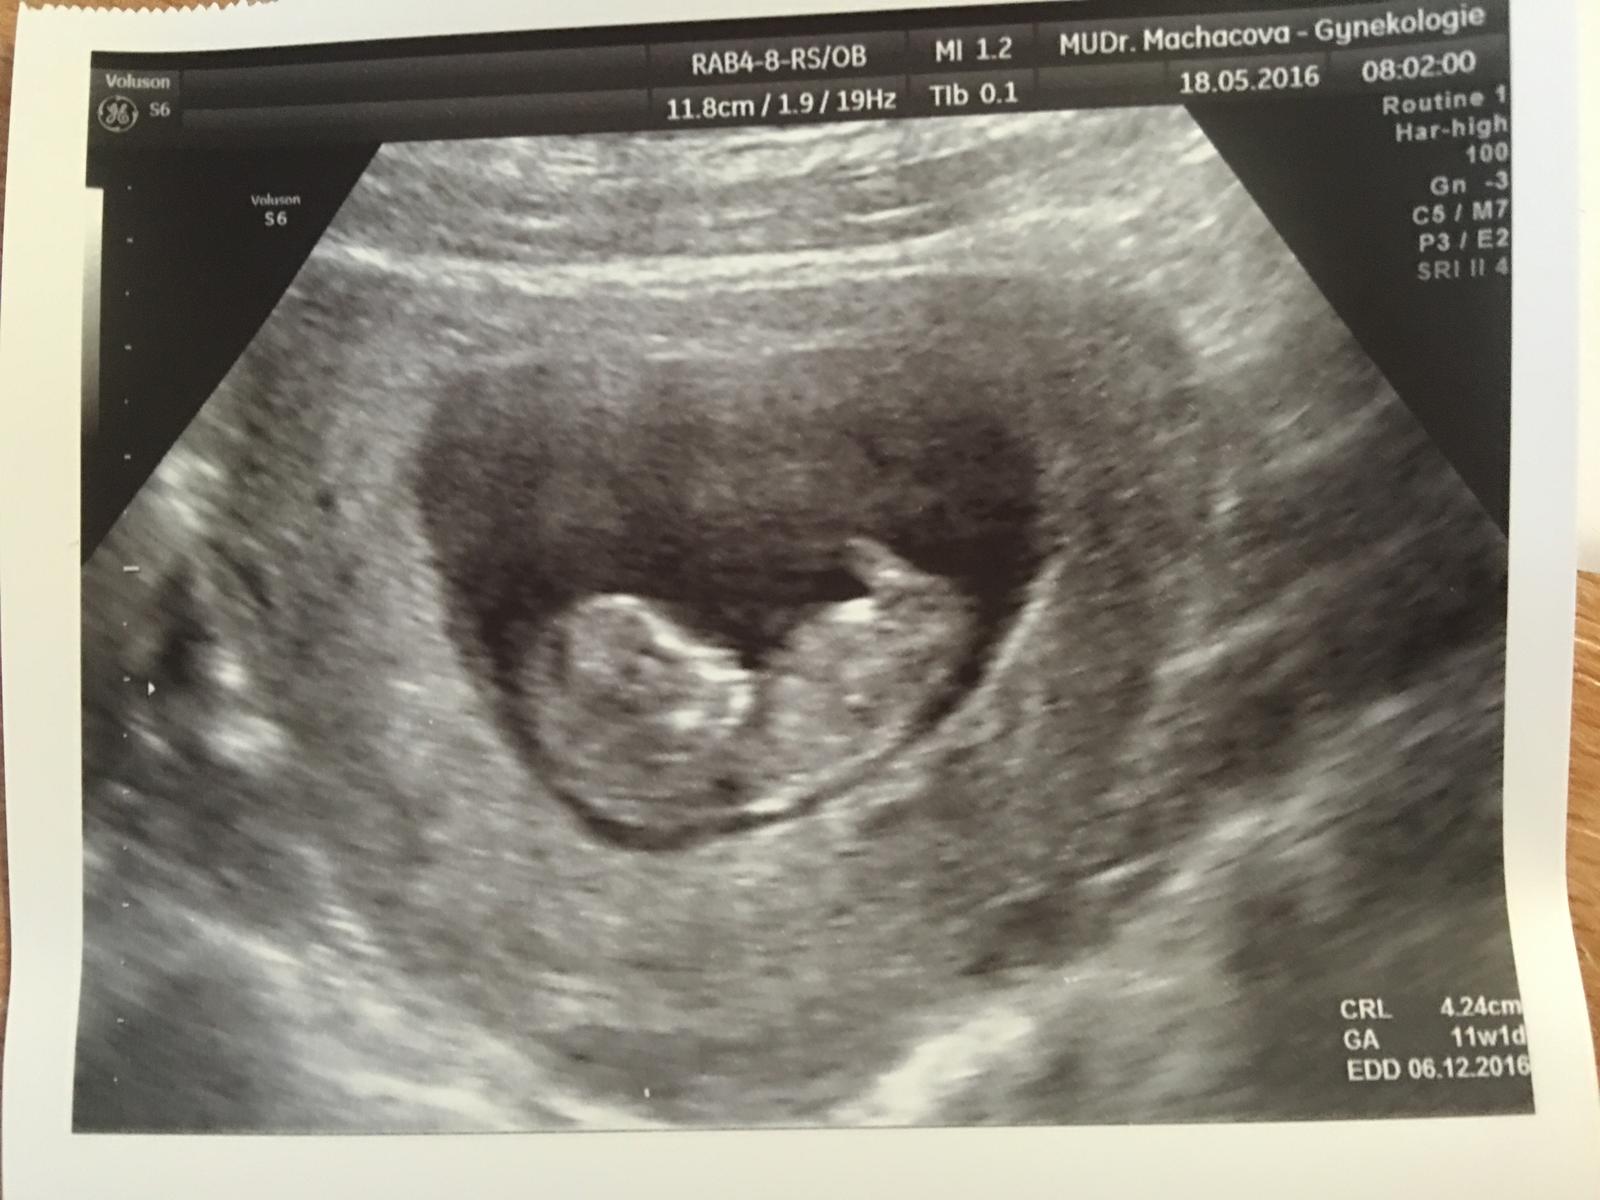

Tááááák!!! Dnešní kontrola naprosto v pořádku!! Moč v pořádku!! 💜 nám bije o stošest..vyrostli sme na 4,2cm a termín porodu se nám tím pádem posunul na 6.12.!! Dělala nám i takový předčasný prvotrimestrální screening (nosní kůska je a nuchální projasnění je v normě) takže sem o něco klidnější!! Mimčo si cucalo paleček a vesele se převalovalo ve vodičce 🙂 bude to asi plavec :D Další kontrola 15.6. a mezitím 2.6. prvotrimestrální screening 🙂 🙂 🙂 Sem nadšena 🙂